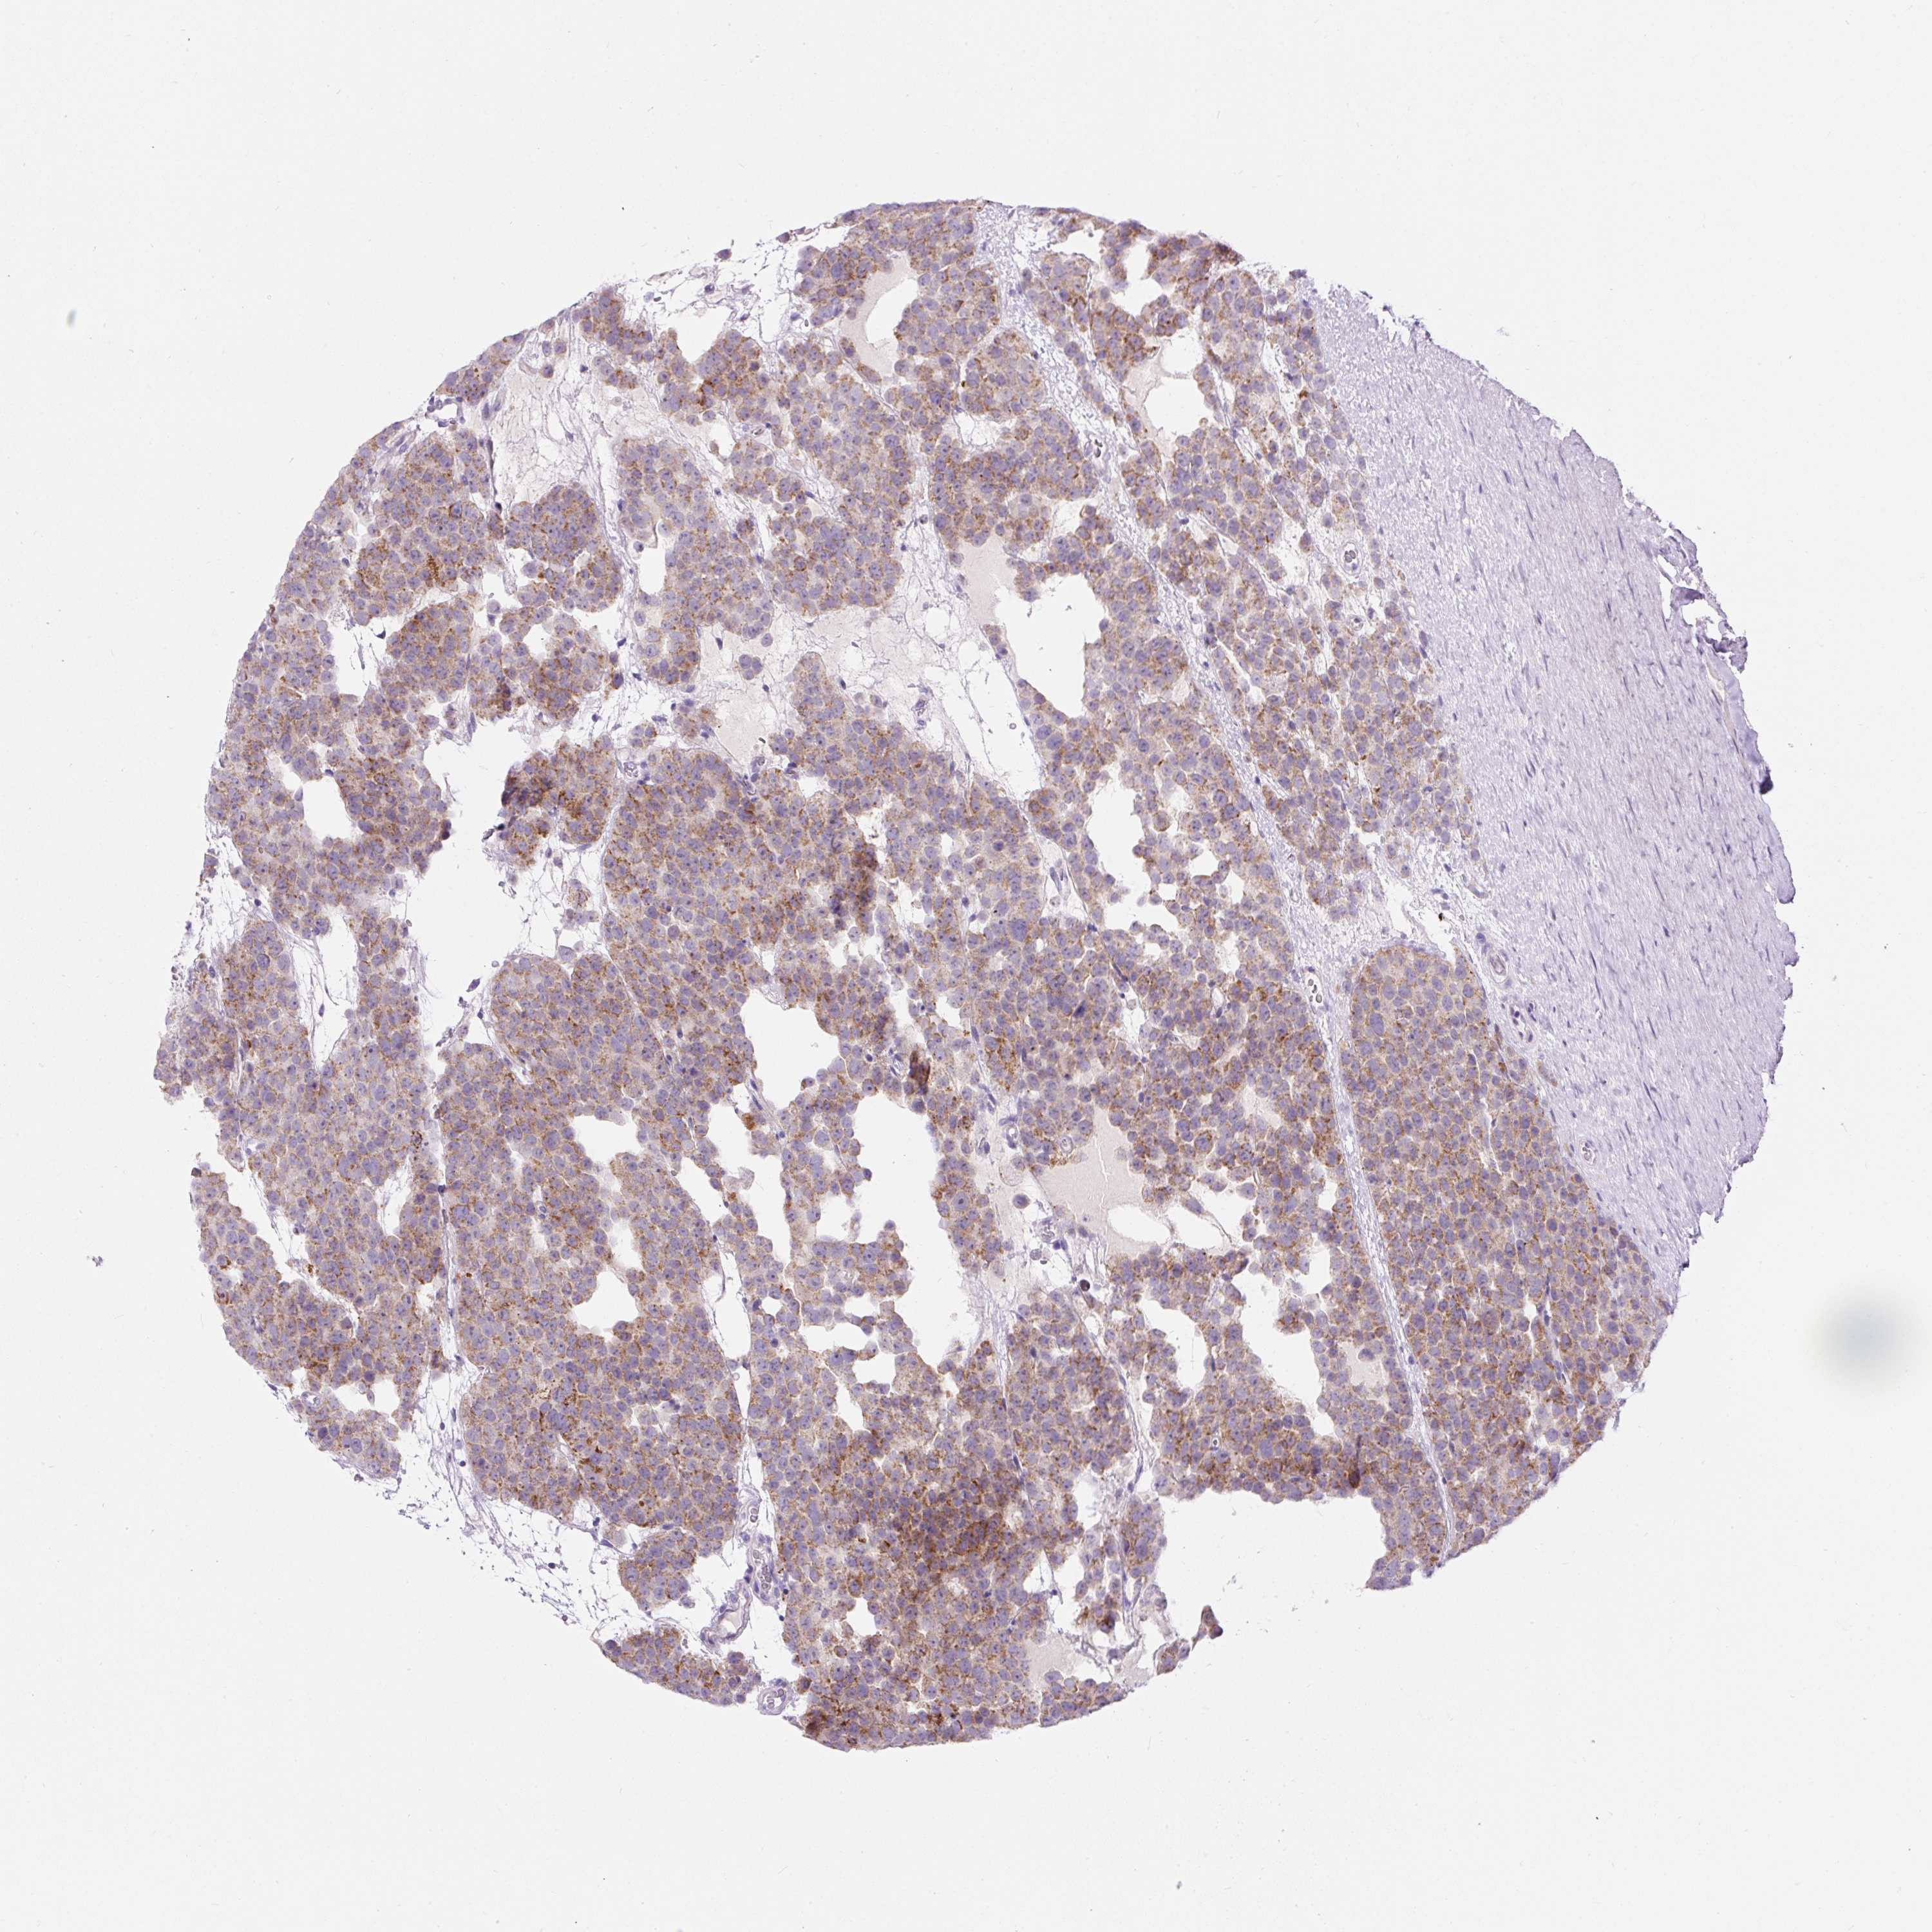

TESTIS CANCER - Protein expressioni

A mouse-over function shows sample information and annotation data. Click on an image to view it in a full screen mode. Samples can be filtered based on level of antibody staining by selecting one or several of the following categories: high, medium, low and not detected. The assay and annotation is described here.

Note that samples used for immunohistochemistry by the Human Protein Atlas do not correspond to samples in the TCGA dataset.

Antibody stainingi

Antibody staining in the annotated cell types in the current human tissue is reported as not detected, low, medium, or high, based on conventional immunohistochemistry profiling in selected tissues. This score is based on the combination of the staining intensity and fraction of stained cells.

Each image is clickable and will lead to virtual microscopy that enables deeper exploration of all samples and also displays staining intensity scores, fraction scores and subcellular localization as well as patient and tissue information for each sample.

Antibody HPA055463

Staining

High

Medium

Low

Not detected

Intensity

Strong

Moderate

Weak

Negative

Quantity

>75%

75%-25%

<25%

None

Location

Nuclear

Cytoplasmic/membranous

Cytoplasmic/membranous,nuclear

Seminoma, NOS

Carcinoma, Embryonal, NOS